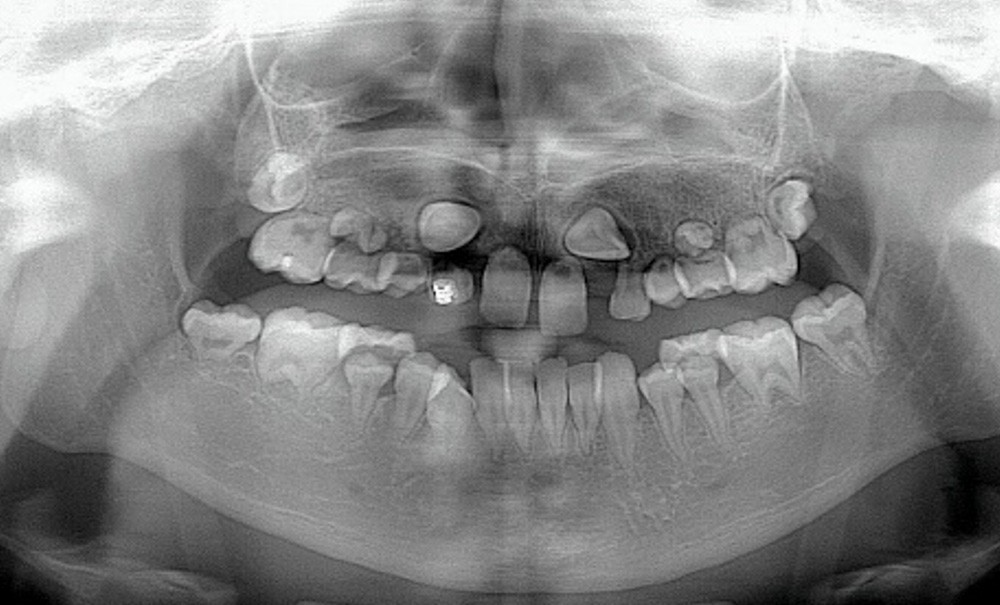

Au niveau endo-buccal, une mobilité des dents maxillaires, en particulier des incisives centrales (11 et 21), est remarquée. Elle peut s’expliquer par les séquelles dentaires du traitement par radio-chimiothérapie, bien visibles sur la radiographie panoramique (fig. 3). Au maxillaire…